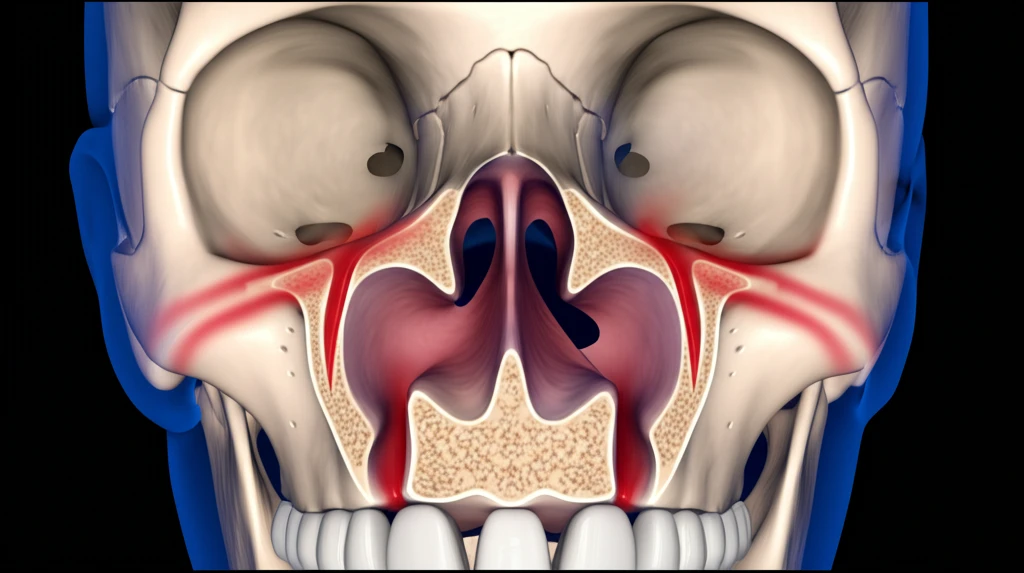

축농증은 약물 치료나 다른 방법으로도 증상이 나아지지 않는 만성 축농증 환자에게 고려됩니다. 특히 다음과 같은 경우에 수술을 생각해 볼 수 있습니다.

- 약물 치료 실패: 항생제, 스테로이드 등으로도 증상이 계속되거나 심해지는 경우

- 심한 증상: 코막힘, 심한 통증, 후각 상실 등으로 일상생활이 어려운 경우

- 합병증 발생: 염증이 눈이나 뇌 주변으로 퍼져 합병증이 생긴 경우

- 물혹 동반: 코 안에 물혹이 있어서 약물 치료로 제거하기 어려운 경우

- 해부학적 구조 이상: 비중격만곡증처럼 코 구조에 문제가 있어 축농증이 자꾸 재발하는 경우

축농증 수술은 주로 내시경 부비동 수술로 진행됩니다. 얇은 내시경을 콧속에 넣어 부비동 입구를 넓히고, 염증 조직이나 물혹 등을 제거하는 방법이죠.